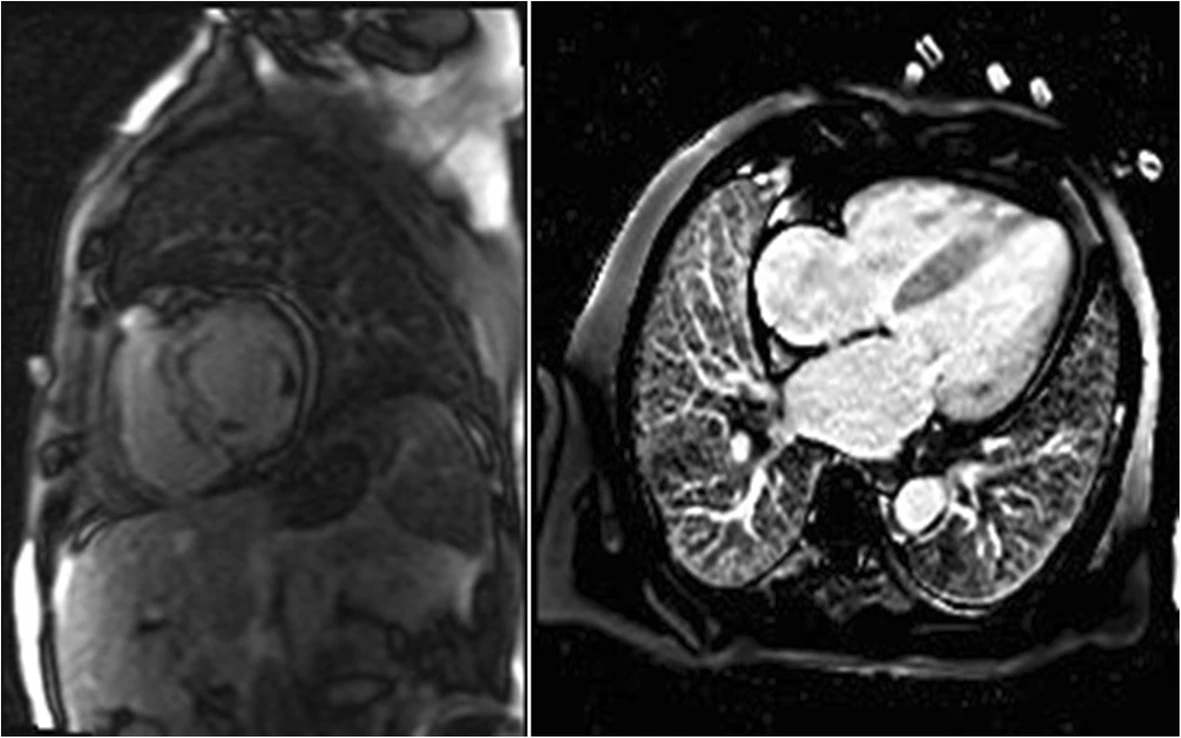

CMR is beneficial in establishing a differential diagnosis among RCM, CP, and infiltrative disorders such as amyloidosis, sarcoidosis, and hemochromatosis. Imaging allows for tissue categorization, including inflammation, and provides high spatial resolution and noninvasive measurement of ventricular volumes. CMR with late gadolinium enhancement (LGE) can assist with diagnosing subtypes of RCM, particularly, amyloidosis and measuring pericardial thickness (Fig. 4). Although not applicable to the RCM diagnosis, CT scans and catheterization with coronary angiography are helpful for eliminating constrictive pericarditis and obstructive coronary artery disease, respectively, from the differential diagnosis. For RCM, chest radiographs show bi-atrial enlargement and in some cases, pulmonary congestion [52].

Fig. 4.Examples of cardiac magnetic resonance (CMR) in differential diagnosis between restrictive cardiomyopathy (RCM) and amyloidosis. Adopted from Kyriakou et al. 2018 [23]. Cardiac magnetic resonance (CMR) images of patients with cardiac amyloidosis. Amyloid fibril deposition pattern mainly affects subendocardial CMR imaging, leading to a shortened T1 relaxation time and a diffuse LGE of the left ventricular endocardium.